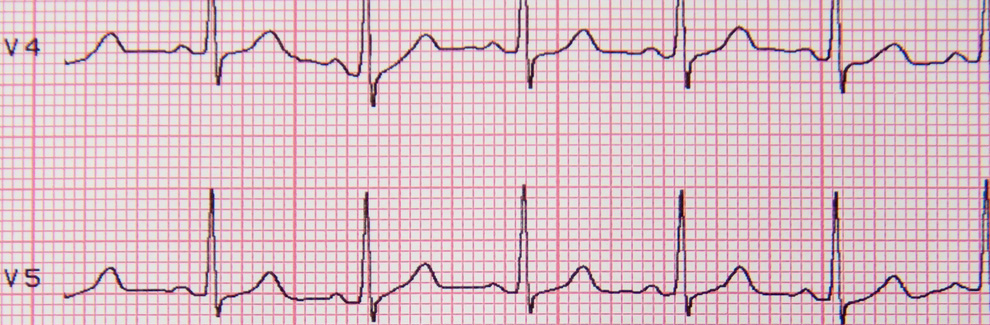

Acute Myocardial Infarction

Myocardial infarction (heart attack) is the leading cause of death in the United States. It is estimated that one in every five deaths in the US is due to a heart attack. Approximately one million patients are admitted to hospitals each year due to heart attacks. 200,000 to 300,000 individuals die from heart attacks before ever receiving medical care. In Case #2 we’ll join 48-year-old Jason Dixon as he experiences a life-threatening heart attack.